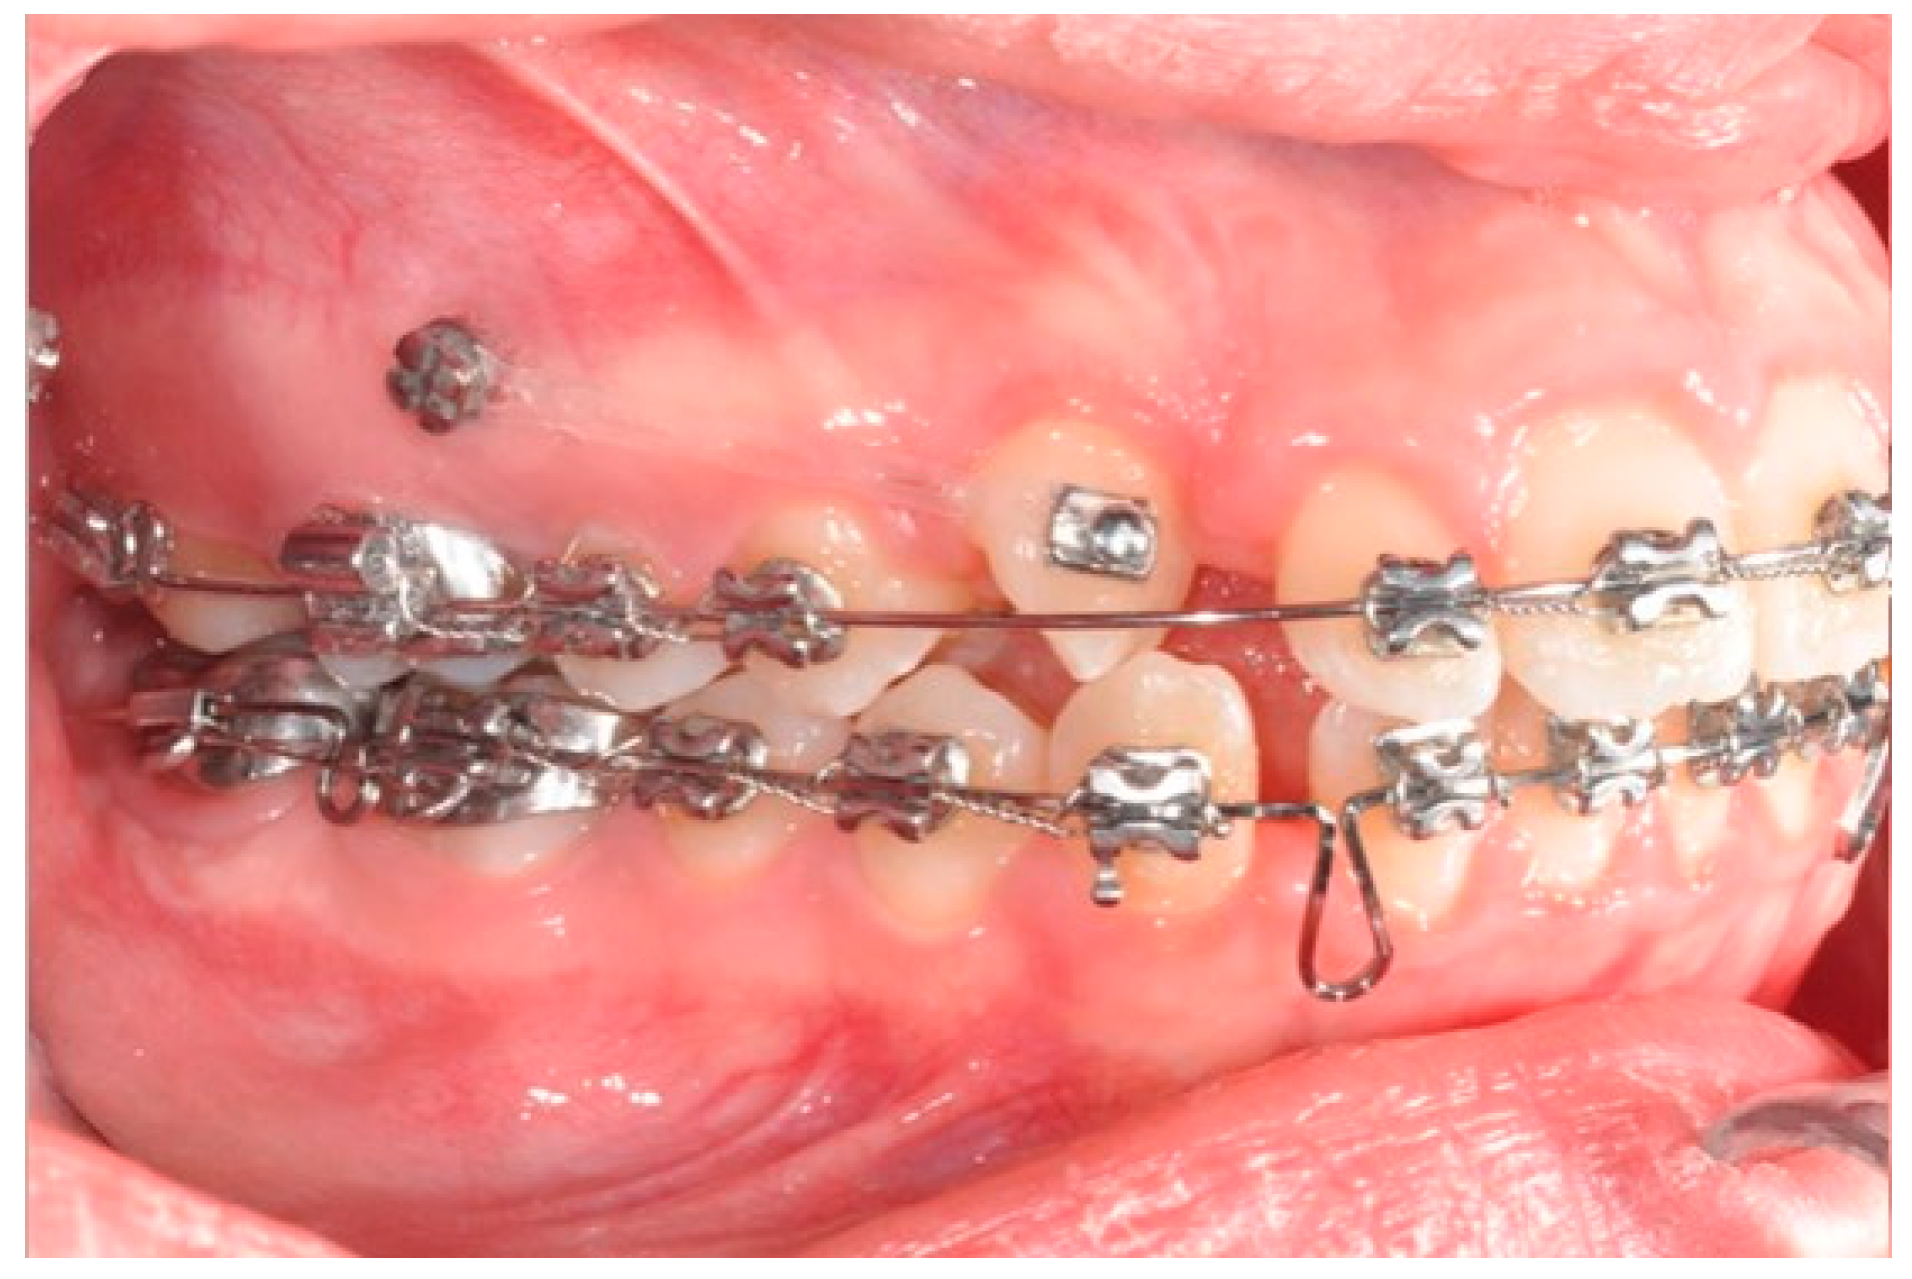

2.3. Canine and Incisor Distalization